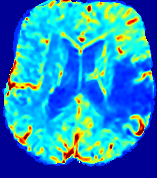

Slice #1Slice #2Slice #3Slice #4Slice #5Slice #6𝐕gt𝟐subscriptnormsuperscript𝐕gt2\|\bf{V}^{\text{gt}}\|_{2}Refer to captionRefer to captionRefer to captionRefer to captionRefer to captionRefer to caption𝐕est𝟐subscriptnormsuperscript𝐕est2\|\bf{V}^{\text{est}}\|_{2}Refer to captionRefer to captionRefer to captionRefer to captionRefer to captionRefer to captionRefer to caption1.51.51.51.21.21.20.90.90.90.60.60.60.30.30.30.00.00.0(mm/s)𝑚𝑚𝑠(mm/s)Destsuperscript𝐷estD^{\text{est}}Refer to captionRefer to captionRefer to captionRefer to captionRefer to captionRefer to captionRefer to caption0.0150.0150.0150.0120.0120.0120.0090.0090.0090.0060.0060.0060.0030.0030.0030.0000.0000.000(mm2/s)𝑚superscript𝑚2𝑠(mm^{2}/s)

Figure 14: PIANO identifiability testing: advection imaging via advection-diffusion. Top row shows 𝐕gt2subscriptnormsuperscript𝐕gt2\|{\bf{V}}^{\text{gt}}\|_{2} used for simulating ground truth pure advection. Rows below show the estimated 𝐕est2subscriptnormsuperscript𝐕est2\|{\bf{V}}^{\text{est}}\|_{2} and Destsuperscript𝐷estD^{\text{est}} on corresponding slices. Note that the plotted value scale for Destsuperscript𝐷estD^{\text{est}} is 0.01 of that for 𝐕gt2subscriptnormsuperscript𝐕gt2\|{\bf{V}}^{\text{gt}}\|_{2} and 𝐕est2subscriptnormsuperscript𝐕est2\|{\bf{V}}^{\text{est}}\|_{2}.

We use the same ‘Advection Imaging’ simulation of Sec. 4.2.1 as the concentration dataset for PIANO. However, instead of modeling pure advection (Eq. 15), we let PIANO estimate both velocity 𝐕estsuperscript𝐕est{\bf{V}}^{\text{est}} and diffusivity Destsuperscript𝐷estD^{\text{est}} via the advection-diffusion PDE (Eq. 2) underlying the proposed PIANO model. Fig. 14 shows the estimated 𝐕est2,subscriptnormsuperscript𝐕est2\|{\bf{V}}^{\text{est}}\|_{2}, and Destsuperscript𝐷estD^{\text{est}} fields for one patient. Although PIANO has the freedom to estimate both a velocity and a diffusivity field from pure advection, PIANO differentiates well between advection and diffusion: the estimated 𝐕est2subscriptnormsuperscript𝐕est2\|{\bf{V}}^{\text{est}}\|_{2} successfully reproduces the ground truth 𝐕gt2subscriptnormsuperscript𝐕gt2\|{\bf{V}}^{\text{gt}}\|_{2} governing the simulated advection process, just as it already did in the ‘Advection Imaging via Advection’ test (Fig. 12). More importantly, the estimated diffusivity Destsuperscript𝐷estD^{\text{est}} is orders of magnitudes smaller than 𝐕est2subscriptnormsuperscript𝐕est2\|{\bf{V}}^{\text{est}}\|_{2}, indicating the estimated diffusion is negligible compared to the estimated advection, which is highly consistent with the underlying pure advection of the simulated data.